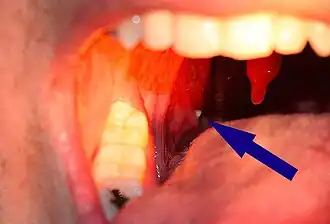

Fotografía de un tonsilolito alojado en una cripta amigdalar. | ||

Los tonsilolitos son concreciones sanguíneas (cálculos) que se forman en las criptas de las amígdalas palatinas, formados por sales cálcicas o en combinación con otras sales minerales, y suelen medir menos de 1 cm.[1]